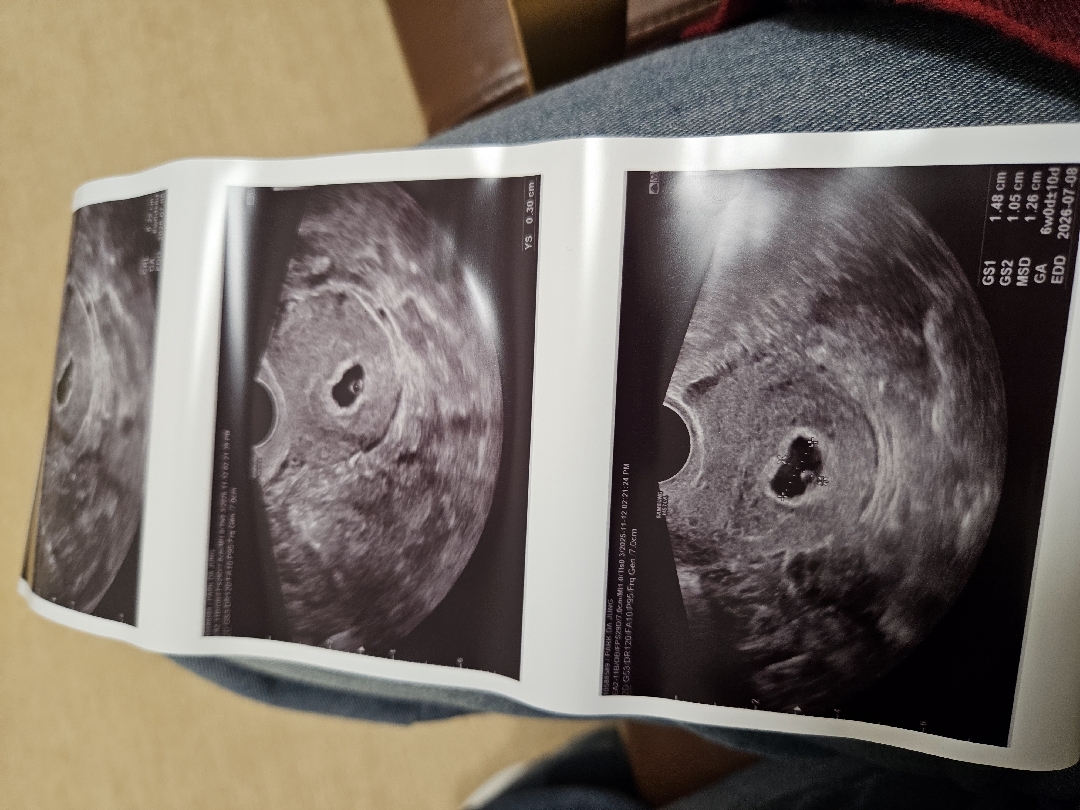

지난 5월 1차시험관 아기가 7주차쯤 심장이 안뛰어서 계류유산으로 보내주고 몸도 마음도 추스리고 정리해서 10월22일에 2차 시험관해서 수요일에 5주차 아기집,난황 보고 왔어요 PGT시험관 5일 동결배아 2차이식이고 출혈도 없고 피고임 없고 완벽히 잘 계신다고 하시네요 26년 7월 출산예정으로 받아왔어요 소화가 잘되는데 소화안되는 느낌에 먹는건 그냥 먹는데 가끔 계란,육류에서 비린맛이 느껴져요ㅠ 이얘기 선생님한테 했더니 입덧약 처방해주셨네요